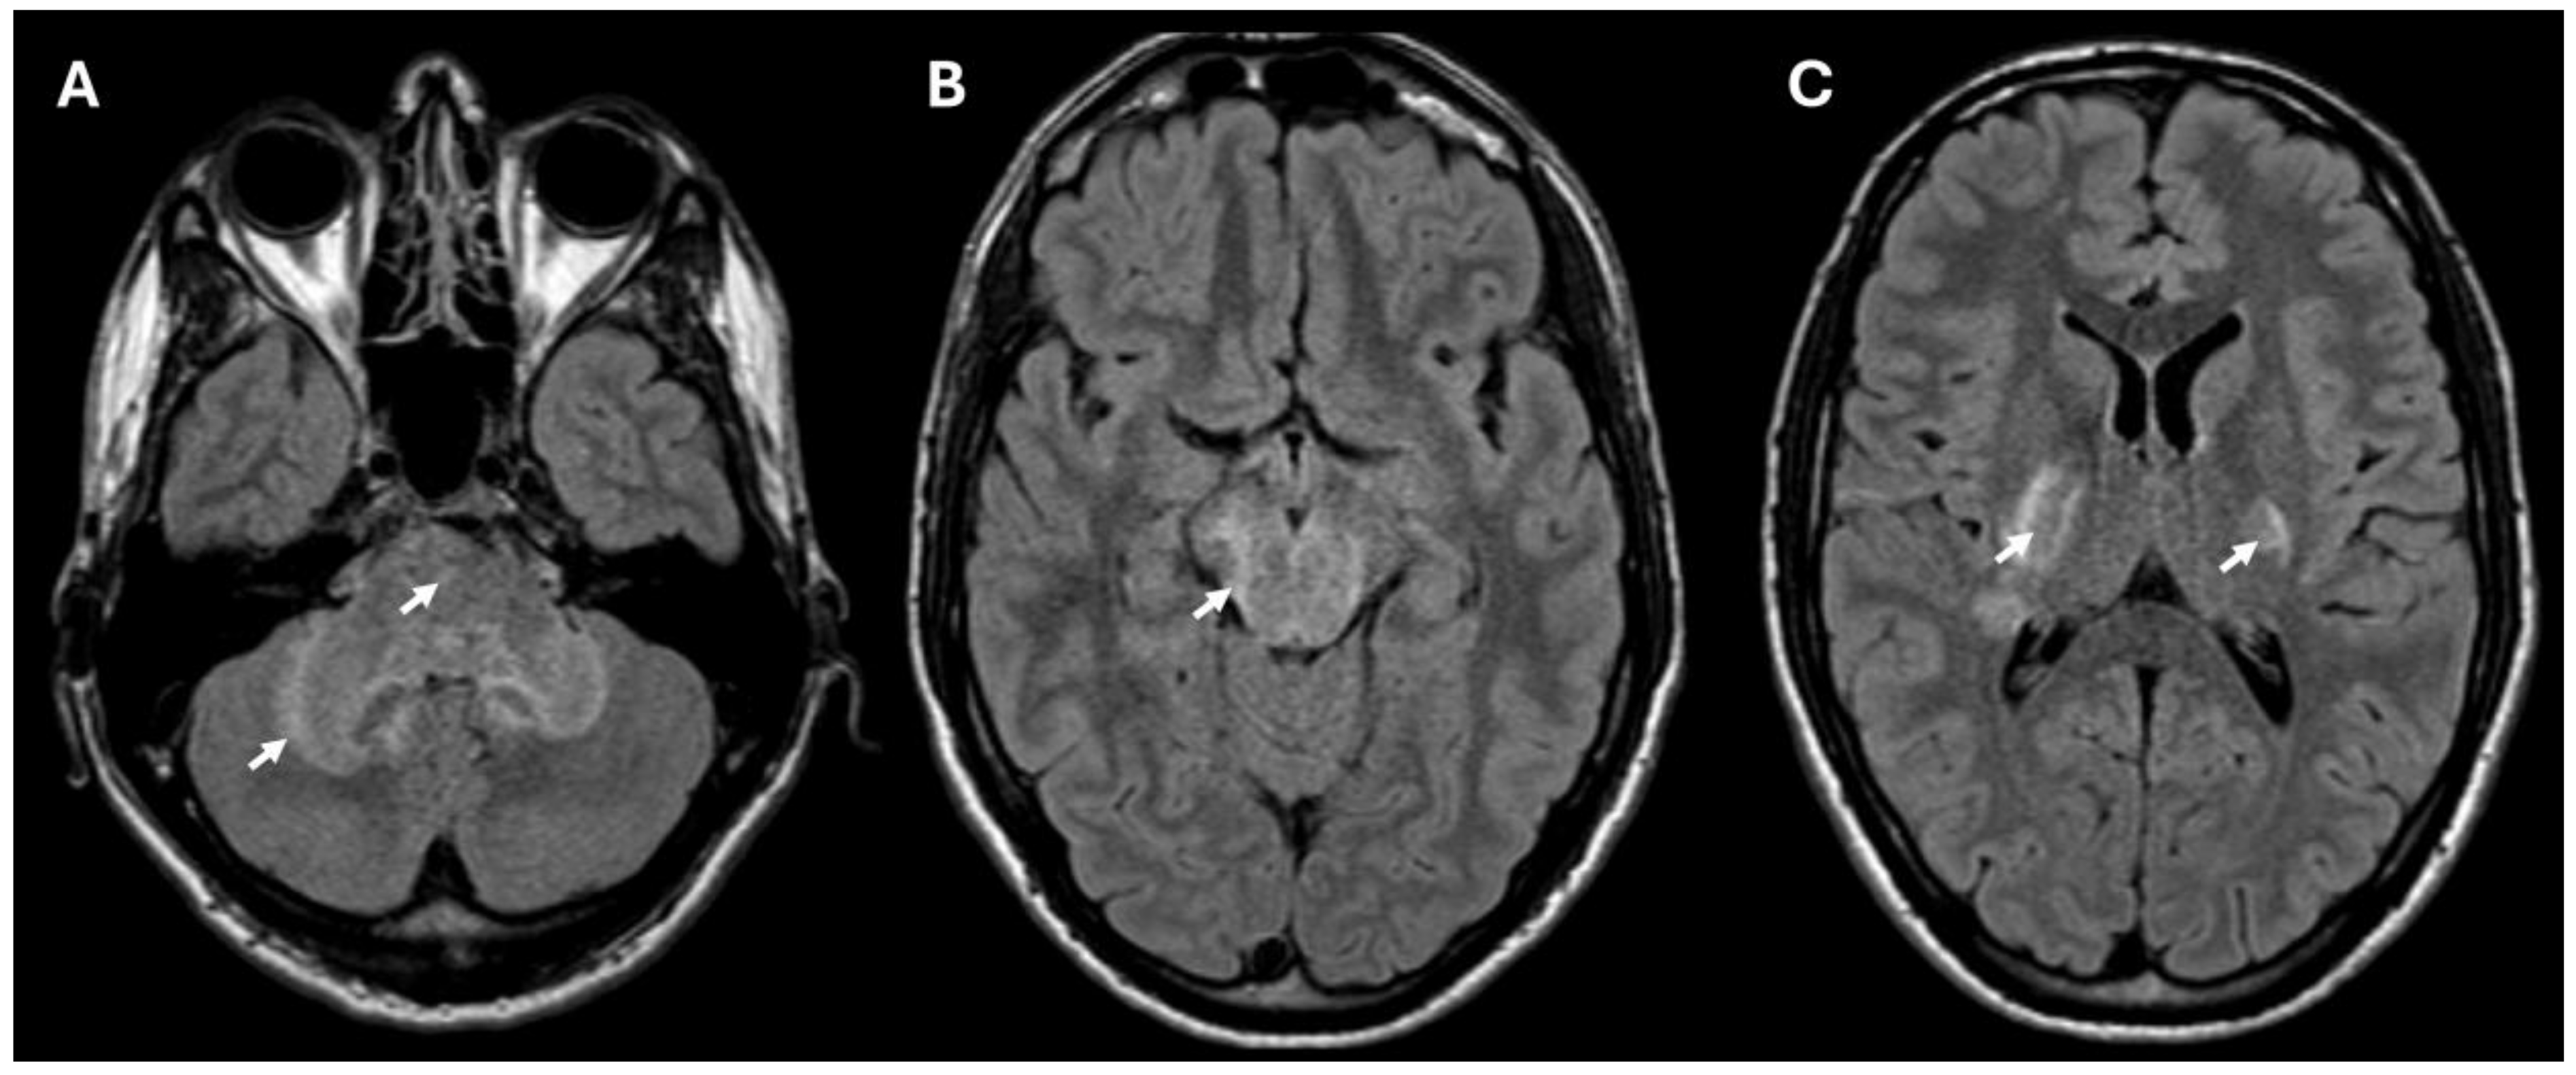

2. Case Presentation